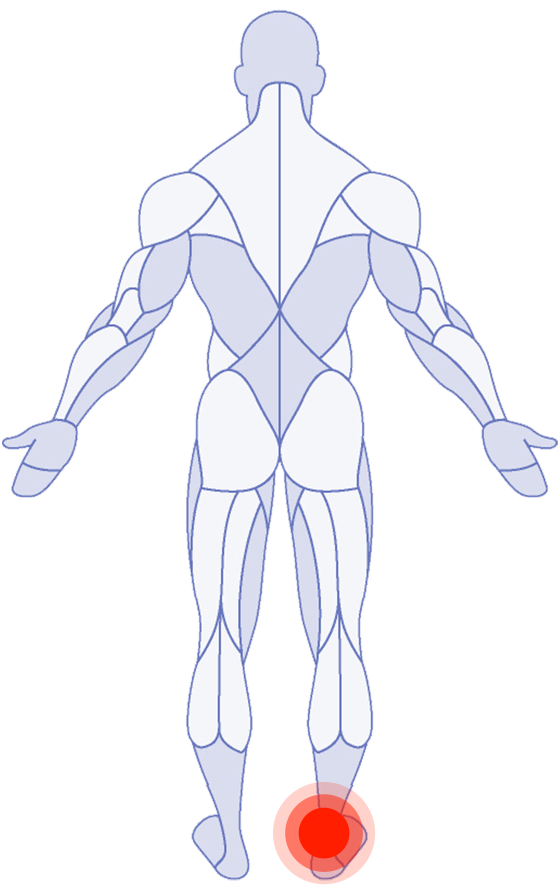

Where do you need attention?